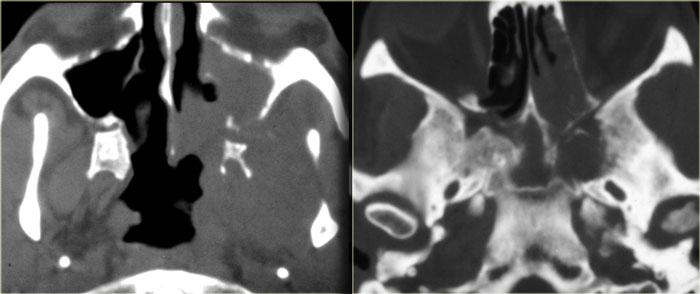

Bên trái là hình ảnh CT của một bệnh nhân sau ghép phổi có sốt và liệt nhiều dây thần kinh sọ tiến triển nhanh.

Chúng tôi sẽ trình bày hình ảnh CT và MRI của bệnh nhân này. Chẩn đoán u lympho được xác định qua sinh thiết.

Trước tiên hãy nghiên cứu các hình ảnh để đánh giá mức độ lan rộng của bệnh.

Sau đó tiếp tục đọc.

Trên hình ảnh CT, các phát hiện bao gồm:

- Khối mô mềm trong xoang hàm (mũi tên đỏ).

- Phá hủy thành xoang (mũi tên vàng).

- Tái cấu trúc và phá hủy xương chân bướm (mũi tên xanh dương).

- Khối mô mềm lớn trong khoang cơ nhai (dấu hoa thị).

Hình ảnh bên phải ở mức cao hơn.

Có hình ảnh mờ đục xoang bướm kèm phá hủy và loãng xương bướm.

CT thể hiện rõ sự phá hủy xương và một phần xâm lấn mô mềm.